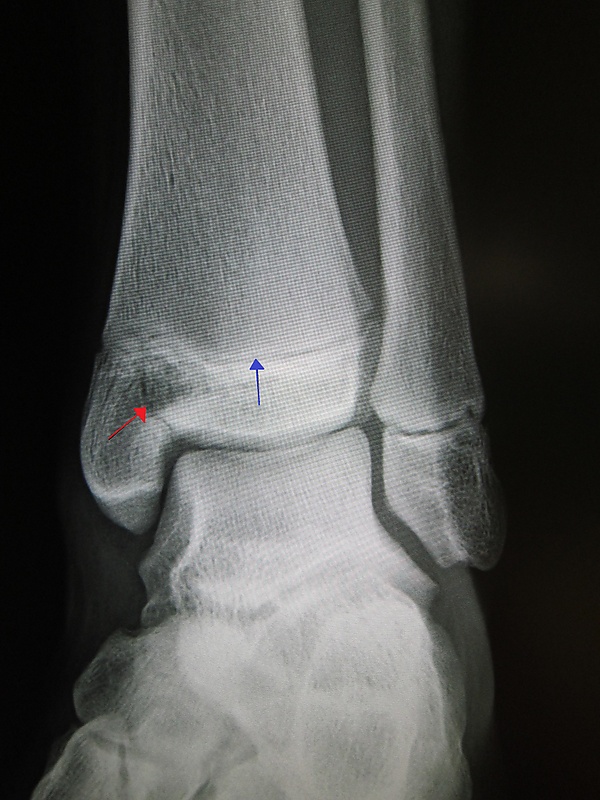

Изображения эпифизеолиза

Рентгеновские снимки переломов Салтера-Харриса с вставками где показаны линии перелома